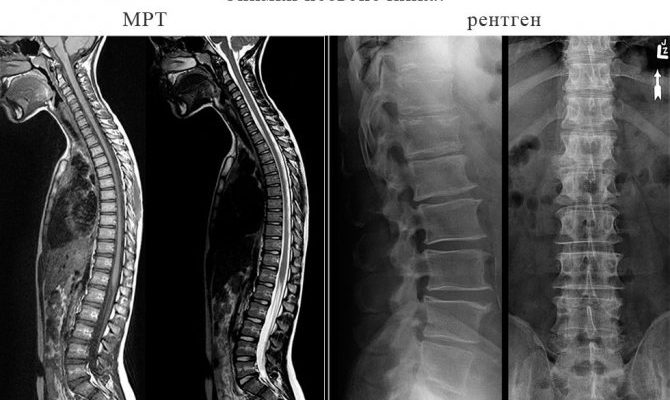

Что выбрать рентген или МРТ при обследовании позвоночника

Оба метода дают полную информацию, но отличаются принципом действия, разницей в способах достижения результата.

Какой метод информативнее

При попытке получить объективную оценку точности и информативности обоих типов исследований учитывается, что они не взаимозаменяемы и используются в разных случаях и ситуациях. Между тем различия в МРТ очевидны:

1. Диагностика с помощью томографии дает большую точность, чем рентген.

4. Предоставляет подробные изображения позвоночника.

С помощью рентгена получить детальные изображения проблематично, так как функциональность устройства ограничена, хуже, чем при МРТ.

Оба вида диагностики отличаются высокой точностью и информативностью, тем не менее, характер предполагаемой патологии определяет выбор.

Магнитно-резонансная томография подходит для исследования мягких тканей, а рентгенологическое обследование врачи рекомендуют при нарушениях целостности костных структур и скелета.